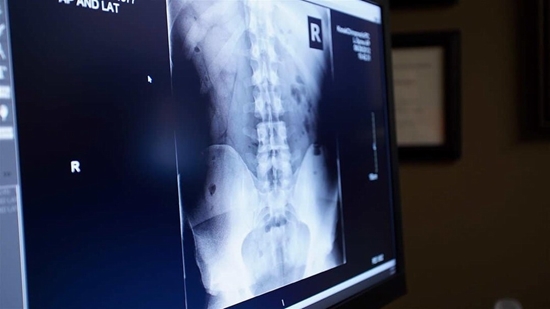

ﭘﺲ از اﻳﻨﻜﻪ ﭘﺰﺷﻚ ﺑﺎ ﻣﻌﺎﻳﻨﻪ ﻛﺎﻣﻞ عصبی و اﺳﺘﻔﺎده از روﺷﻬﺎى ﺗﺼﻮﻳﺮ ﺑﺮدارى ﻣﺜﻞ SCAN ,CT MRI و ﻧﻮار ﻋﺼﺐ و ﻋﻀﻠﻪ، ﺑﻴﺮون زدگی دﻳﺴﻚ ﺑﻴﻦ ﻣﻬﺮه اى را ﺗﺸﺨﻴﺺ داد، ﺑﺮ اﺳﺎس ﺷﺪت ﺑﻴﻤﺎرى روش درﻣﺎن را اﻧﺘﺨﺎب ﺧﻮاﻫﺪ ﻛﺮد.